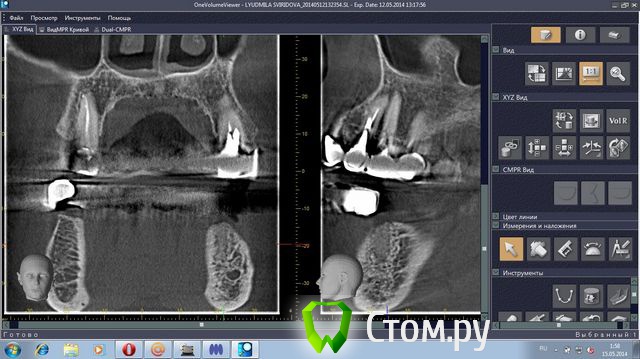

stradalitca Опубликовано 18 мая, 2014 Поделиться Опубликовано 18 мая, 2014 Здравствуйте! у меня проблема такая. за последние 4 года мне удалили нижний центральный зубик (киста была), пролечили каналы в нижних зубах. Поставили мост с металлокерамики. Он простоял некоторое время, а потом( год-два) просто стал качаться. Его раза три сажали заново на цемент( прошлым летом). в итоге, пошла в другую клинику. Мост ещё раз сняли( он держался на честном слове). Оказалось, что пятёрка снизу слева пробита вкладкой. Зуб удалили. На сдедующий день обточили ещё зубы некоторые и сняли слепок под новые пару вкладок. через неделю поставили на цемент( сразу на цемент, без времянки)НОВЫЙ мост. Это было в конце декабря. Через две недели десну разнесло и прищлось резать, выпускать гной( надрез примерно под тройкой слева). Сейчас опять явный свищ примерно под 3-4 нижними слева.Сделали рентген - оказалось, что тройка имеет два корня и она пробита вкладкой. Теперь даже не знаю что делать. Просто резать десну и опять чистить? Врач говорит, что надо снять мост и удалить тройку. Другой врач говорит, что тройку может и можно спасти, надо снять мост, убрать вкладку и смотреть, что с тройкой. На прошлой неделе сделала объёмный рентген. Сама неделю копалась в программе, разглядывя свою нижнюю челюсть. мне показалось, что там маячит какой-то остаток корня шестёрки слева( мне его сто лет назад удаляли). Пожалуйста, подскажите, что делать? какие перспективы и варианты есть на мои нижние зубы?Заранее большое спасибо за все ваши ответы и мнения.Скриншоты с программы 3D прилагаю.или может надо мост снять, выдернуть тройку слева и поставить металлопластмассу?( верхние зубы тоже штук 8 слитно металлокерамика, ставили первый паз отдновременнно нижние и верхние) Ссылка на комментарий

stradalitca Опубликовано 20 мая, 2014 Автор Поделиться Опубликовано 20 мая, 2014 (изменено) Добрый вечер! Я тут ещё глянула как установлен штифт на четвёрке снизу справа. Вот фото в проекциях. Неужели зуб тоже пробит штифтом? или пойдёт ? и я зря переживаю. Изменено 20 мая, 2014 пользователем stradalitca Ссылка на комментарий